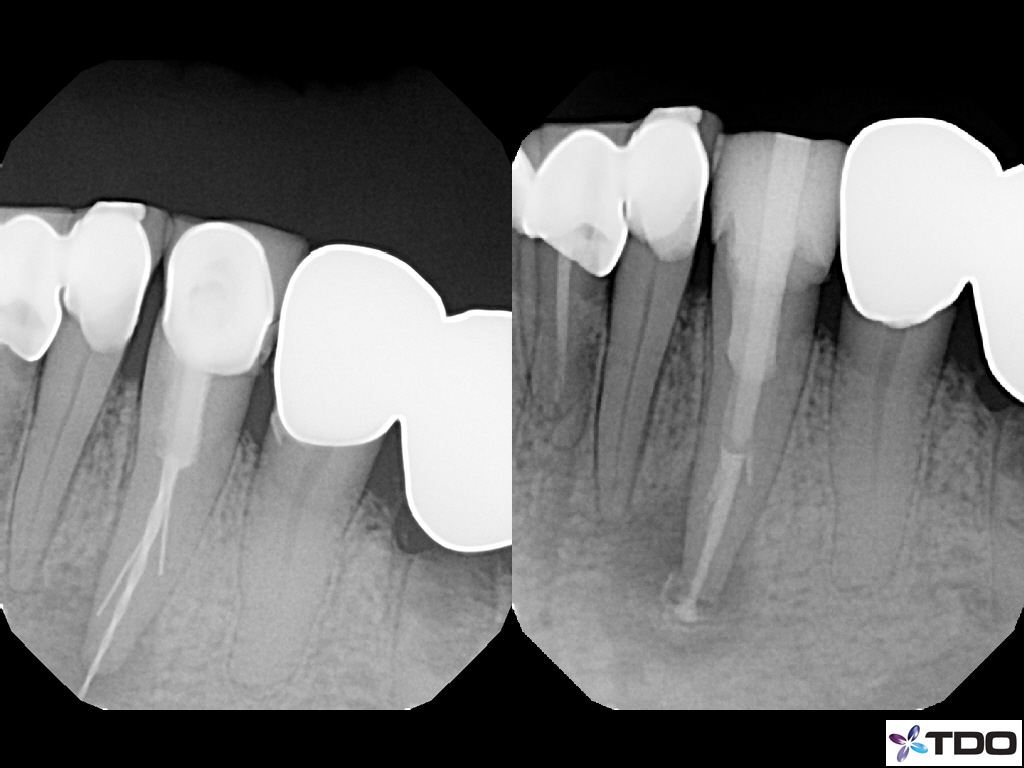

These cases show a level of commitment to conservative endodontics rarely seen in endo today. Plus the restorative excellence is inspiring and should stimulate all endodontists to up their game and help others realize how important the restorative aspect of endodontics is.

Beautiful work Pushpak. How many of these were X-Nav?